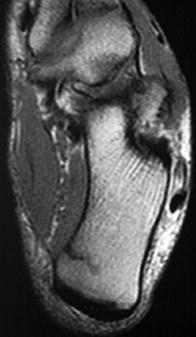

女,48岁,長跑运动员,左跟骨部痛,结合图像,最可能的诊断是 ( )A、左踝关节退行性变B、应力性骨折C、左跟骨骨髄炎D、结核...

问题 女,48岁,長跑运动员,左跟骨部痛,结合图像,最可能的诊断是 ( )

选项 A、左踝关节退行性变 B、应力性骨折 C、左跟骨骨髄炎 D、结核 E、未见异常

答案 B